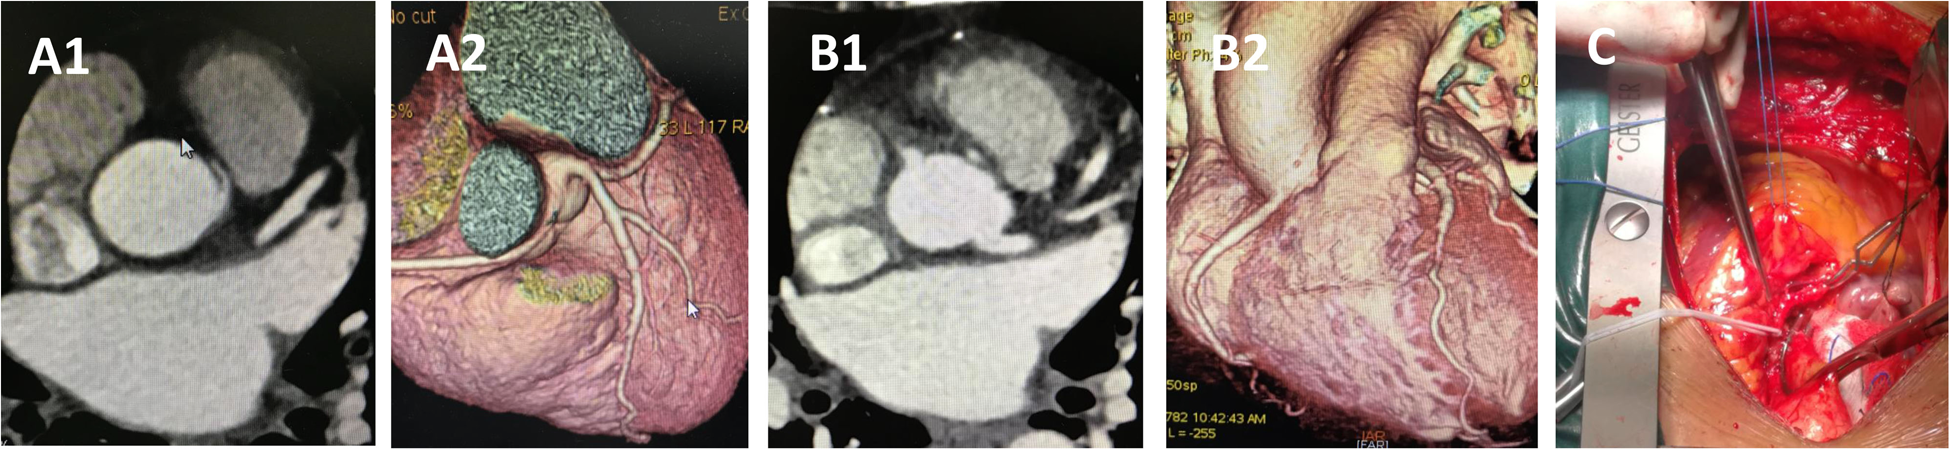

Figure 6

CCTA of case 10 underwent reimplantation. (A) Preoperative images showing anomalous right coronary artery arising from the left sinus. (B) Follow-up images showing proximal right main coronary artery without visible stenosis. (C) Intraoperative picture showing the reimplantation procedure without cardiopulmonary bypass. CCTA, coronary computed tomography angiography.

Case 10, a 47-year-old woman, presented with dyspnea for 2 months before surgery. Coronary angiography and CCTA revealed that the RCA originated from the left coronary sinus with an IAC between the aorta and pulmonary artery. The procedure was performed through a median sternotomy without cardiopulmonary bypass (Supplementary Video S1). After determining that the origin segment of the RCA was of sufficient length, and following adequate mobilization of the RCA and 1 min of ischemic preconditioning, the aorta was partially cross-clamped, and the RCA was clamped with vascular clips at both the emergence and a distal point. The RCA was then transected at a normal point proximal to the stenosis. A 5 mm hole was punched into the right coronary sinus, and the RCA was reimplanted in an end-to-side fashion using continuous 5-0 polypropylene sutures. The stub of the RCA was closed by oversewing it to the aortic wall using 7-0 polypropylene sutures. The total cross-clamping time for the RCA was 5 min. Hemodynamics were stable throughout the procedure, and the patient reported no postoperative complaints. Follow-up CT at 6 months confirmed that the repaired coronary artery remained patent. To the best of our knowledge, this is the first reported case of RCA reimplantation without cardiopulmonary bypass.